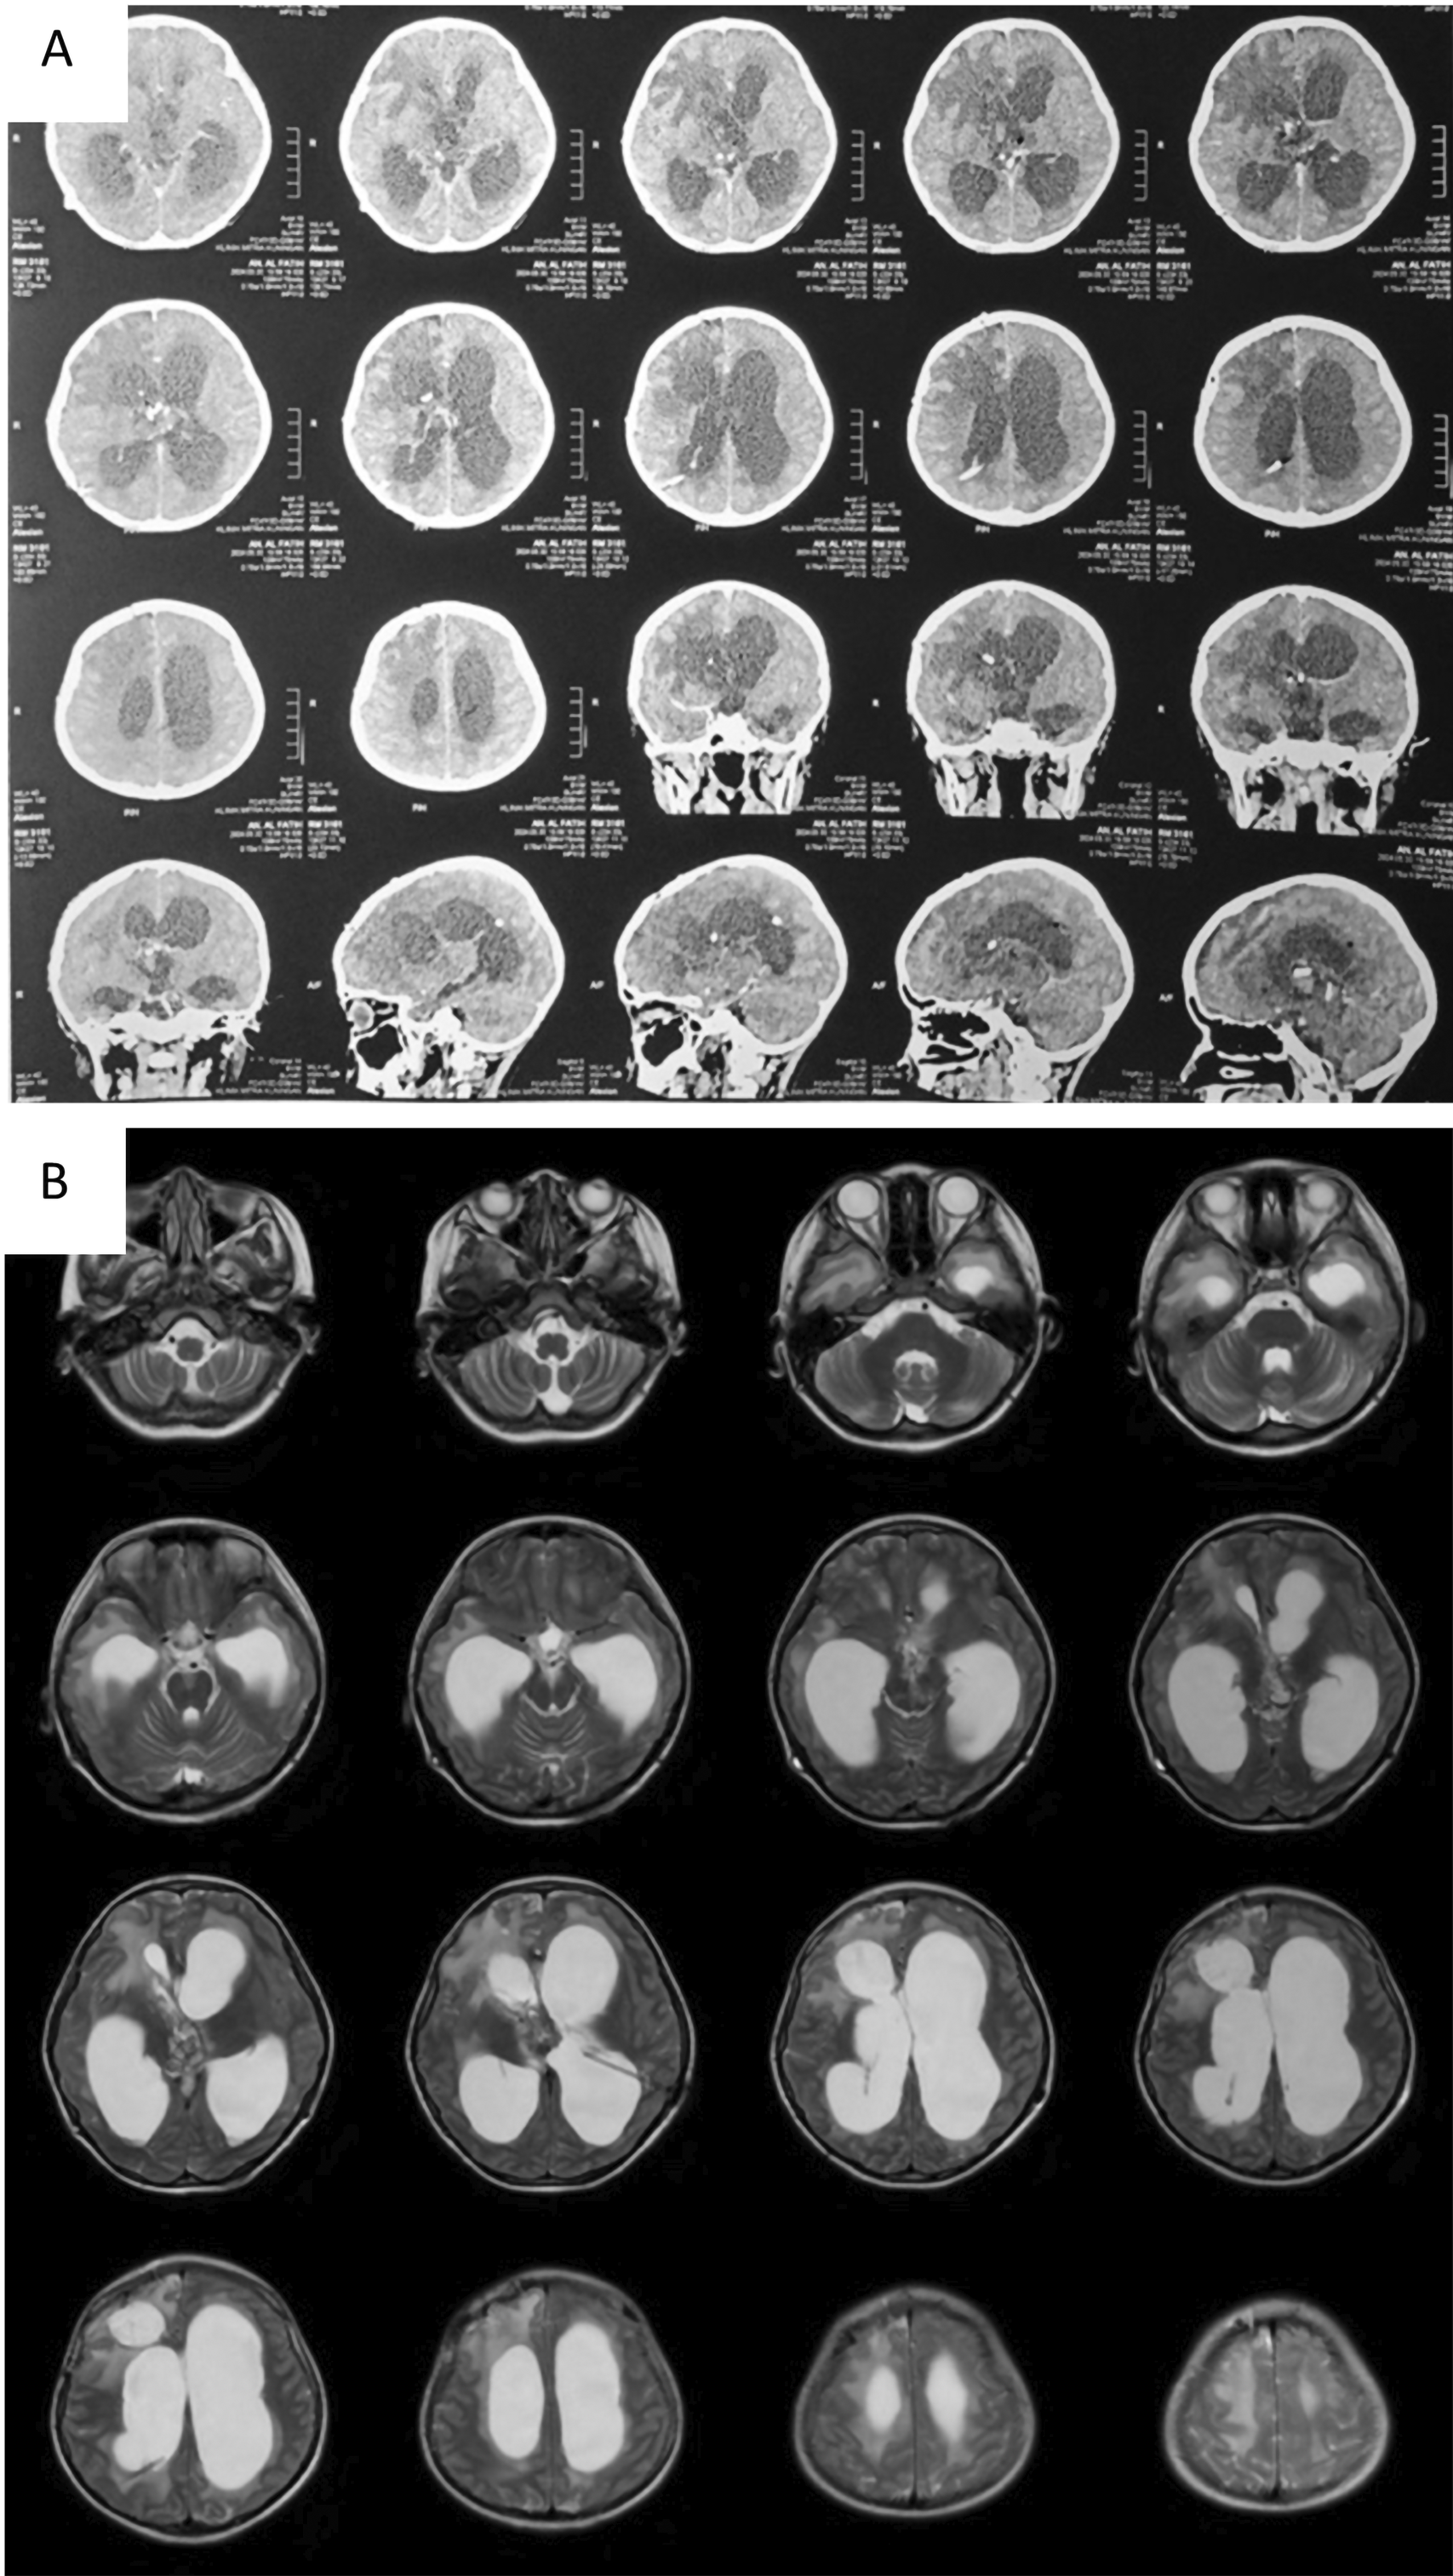

Tumor removal was performed through a transfrontal transcortical transventricular approach towards the 3rd ventricle. We aimed for gross total tumor removal and found a multiloculated solid cystic mass with thick glistening greyish content attached to the septum pellucidum and bilateral fornix. Massive bleeding occurred upon removal of the tumor from the bed, and we suspected that the internal cerebral vein was injured. The patient lose almost 1.5 L of blood and suffered from hemorrhagic shock during fluid resuscitation and blood transfusion were being given. We packed the bleeding with cotton patties, and the surgery was stopped for salvage. The patient was sent to the pediatric ICU for stabilization, knocked down for three days, and regained consciousness. Another CT scan revealed intraventricular hemorrhage (Figure 3). We performed another craniotomy to remove the hemostasis pack 10 days later. Histopathological examination revealed a mature teratoma consisting of flat epithelial cells, fat cells, cartilage, chondrocytes, and ciliated pseudostratified epithelial cells (Figure 4). The patient was discharged one week after the 2nd craniotomy. The postoperative CT scan revealed a small remaining intraventricular tumor and hydrocephalus; therefore, another VP shunt was placed on the contralateral side (Figure 5). After surgery, the patient had a GCS score of 15, but the developed left hemiparesis. The clinical timeline is shown in Figure 6.